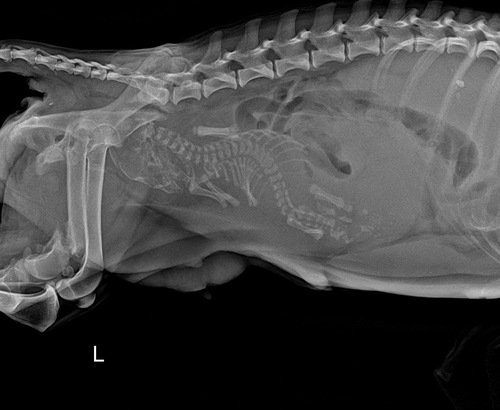

Olá pessoal, estou criando esta vaquinha para ajudar a custear o tratamento da minha cachorrinha. A princesa criou recentemente e um dos filhotes ficou preso dentro dela por 48 horas, nós não sabíamos quantos filhotes tinha então não percebemos, durante essas horas ela não comeu e perdeu sangue, quando levamos ao veterinário ela já estava bem debilitada. Foi preciso fazer um tratamento pra fortalecer e ela conseguir resistir a cesárea. Na cidade onde moramos não conseguimos realizar os procedimentos pois só atendem em horário comercial, levamos para outra cidade em uma clínica veterinária de plantão.